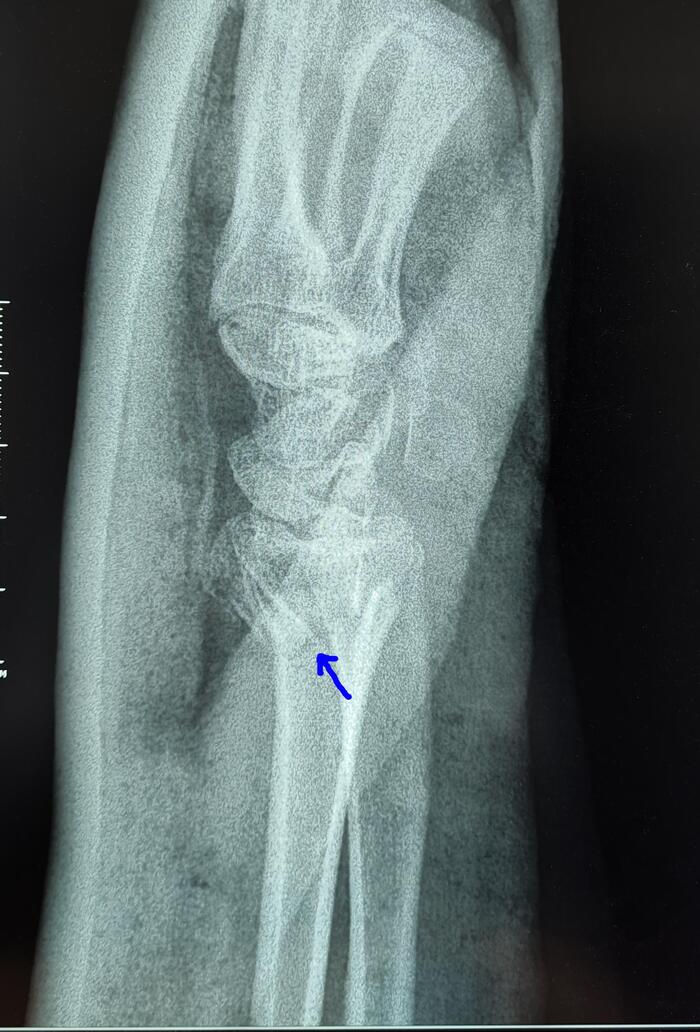

На рентгенограмме костей таза: суставные щели тазобедренных суставов неравномерно сужены, с выраженными краевыми остеофитами в верхне-наружном отделе. Субхондральный склероз суставных поверхностей. Головки бедренных костей уплощены, скошены, структура костной ткани с участками просветления чередующихся с участками остеосклероза. Шейки бедренных костей расширены. Заключение: Двусторонний коксартроз 3 ст. Асептический некроз головок бедренных костей.